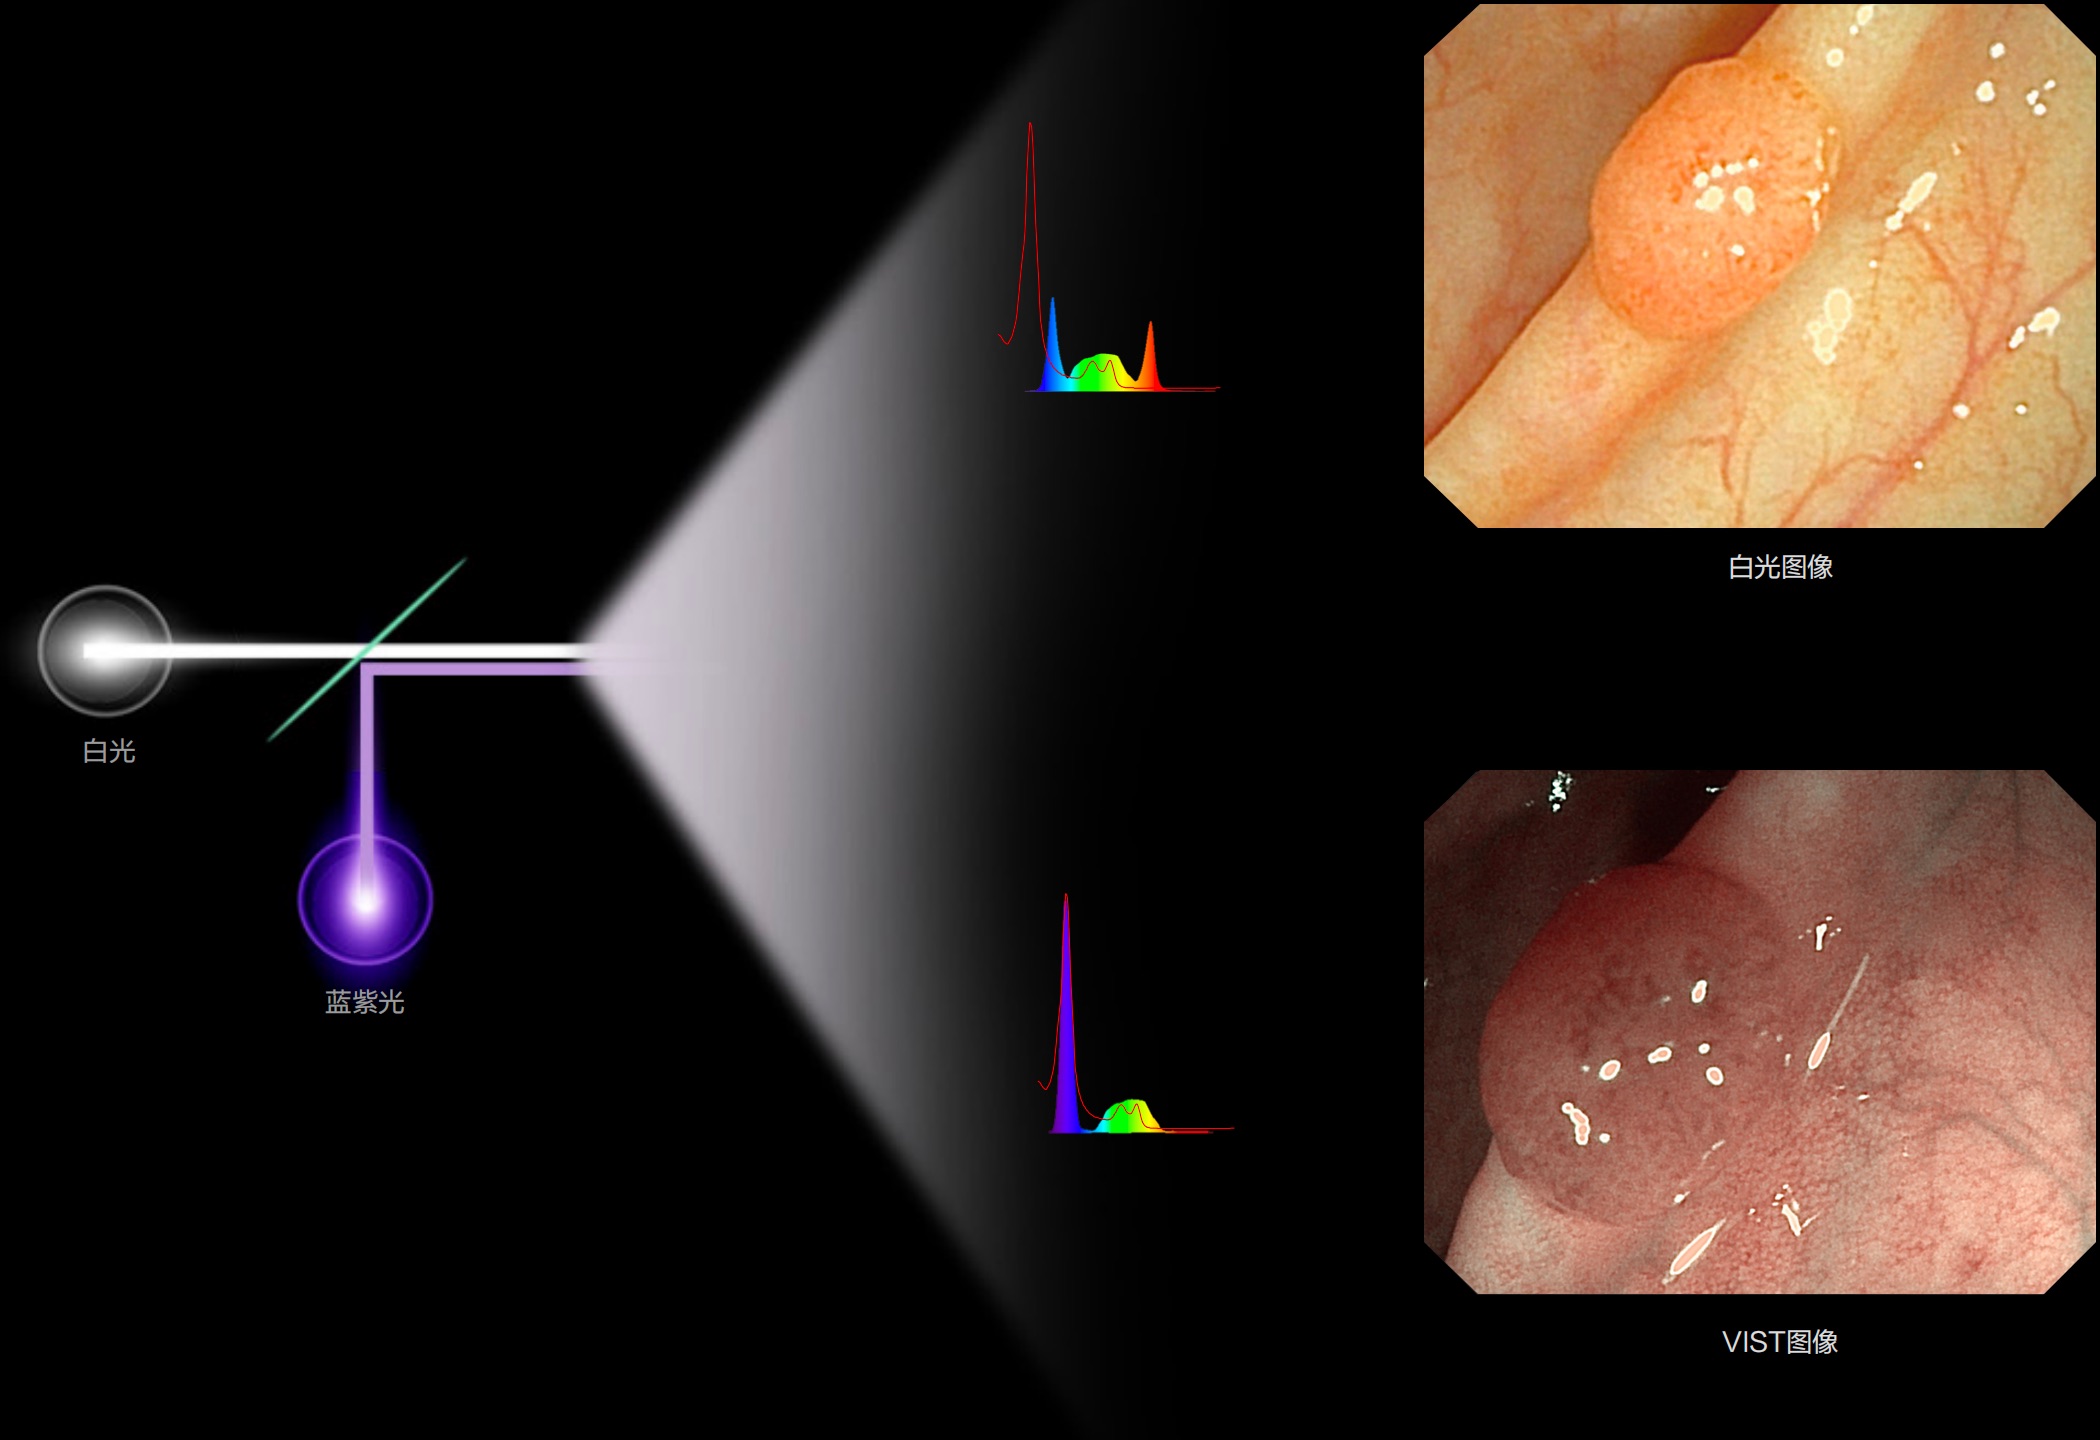

(Versatile Intelligent Staining Technology)

能够凸显黏膜浅层血管轮廓和黏膜表面微结构,适用于中、近景观察下的早癌精确诊断。

(Spectral Focused lmaging, SFI)

能够凸显黏膜浅层和中层血管轮廓,适用于中、远景观察下的病灶识别和早癌筛查。

照明光谱

光谱提取

光谱提取能量汇聚

RGB图像重建

染色模式显示

白光图像

SFI图像